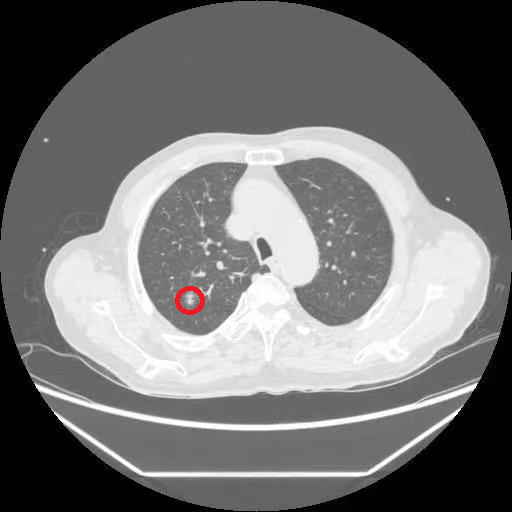

77岁的李老汉(化名)在体检中发现右肺上叶存在一个10×7毫米的高危结节,需进行干预。然而他合并有室性早搏、房性早搏、心功能下降、冠脉狭窄及重度呼吸功能不全等多种疾病,身体状况无法承受全麻手术风险。若不处理病灶,又面临结节进展可能带来的严重后果。

在充分评估病情并取得患者与家属同意后,市一医胸外科团队决定为李老汉实施“肺结节消融术”。手术由放射影像科辜赶超医师与胸外科杜卓副主任医师协同完成。手术团队在CT引导下精确定位病灶,经局部麻醉后,将消融导管经皮穿刺置入结节部位,通过高温热消融仅用时约3分钟即成功灭活病灶。整个操作过程约半小时,患者全程保持清醒,未诉明显不适。